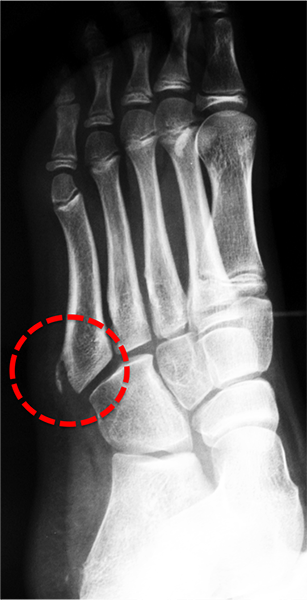

4. Osteocondrose da Base do 5º Metatarso ( Doença de Iselin ):

É a osteocondrose que acomete a base do quinto metatarso e relaciona-se diretamente com a inserção do tendão fibular curto nesta região. Foi descrita por Iselin em 1912.

É uma lesão pouco comum que acomete tanto em meninos quanto em meninas, mas principalmente em jovens esportistas entre 7 e 10 anos.

O paciente queixa-se de dor e inchaço localizado na lateral do pé.

A palpação do local é dolorosa e piora com o movimento forçado de flexão plantar e inversão (movimento do pé para baixo e para dentro).

Ao raio X pode-se observar alargamento da base do 5º metatarso e irregularidade no padrão de ossificação da fise (cartilagem de crescimento).

O tratamento é conservador e consiste em evitar atividades de impacto, uso de medicação analgésica, gelo e, ocasionalmente, imobilização temporária do pé e tornozelo.

A fisioterapia e o retorno gradual à atividade esportiva são liberados após a melhora dos sintomas, que ocorre entre 6 e 12 semanas após o início do tratamento.

A cartilagem de crescimento ou fise da base do 5º metatarso ossifica-se completamente por volta dos 12 e 14 anos de idade.